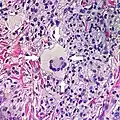

Multinucleated giant cells

- Foreign bodies indicate a foreign body granuloma.

- Specific forms of multinucleated giant cells include the Touton giant cell, which contains a ring of nuclei surrounding a central homogeneous cytoplasm, with foamy cytoplasm surrounding the nuclei.[29][30] The central cytoplasm (surrounded by the nuclei) may be both amphophilic and eosinophilic.[31]

Touton giant cell